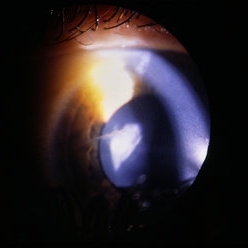

Anterior segment image with subconj heme.

Condition/keywords: trauma